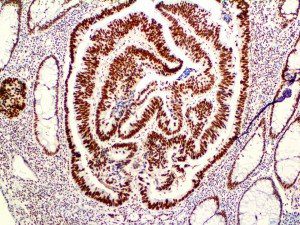

This activation induces inflammatory monocytes to highly express IL-6, starting a localized and then systemic cascade effect that results in hyperproduction of IL-6, which accelerates the inflammatory process. Because IL-6 also increases vascular permeability, excessive levels cause blood vessels to become very leaky. This, along with clotting factors released from vascular endothelial cells, stimulates the coagulation cascade, resulting in microthrombosis (tiny clots), which leads to ischemia and tissue death of the kidney, intestines, heart, liver, brain and extremities.